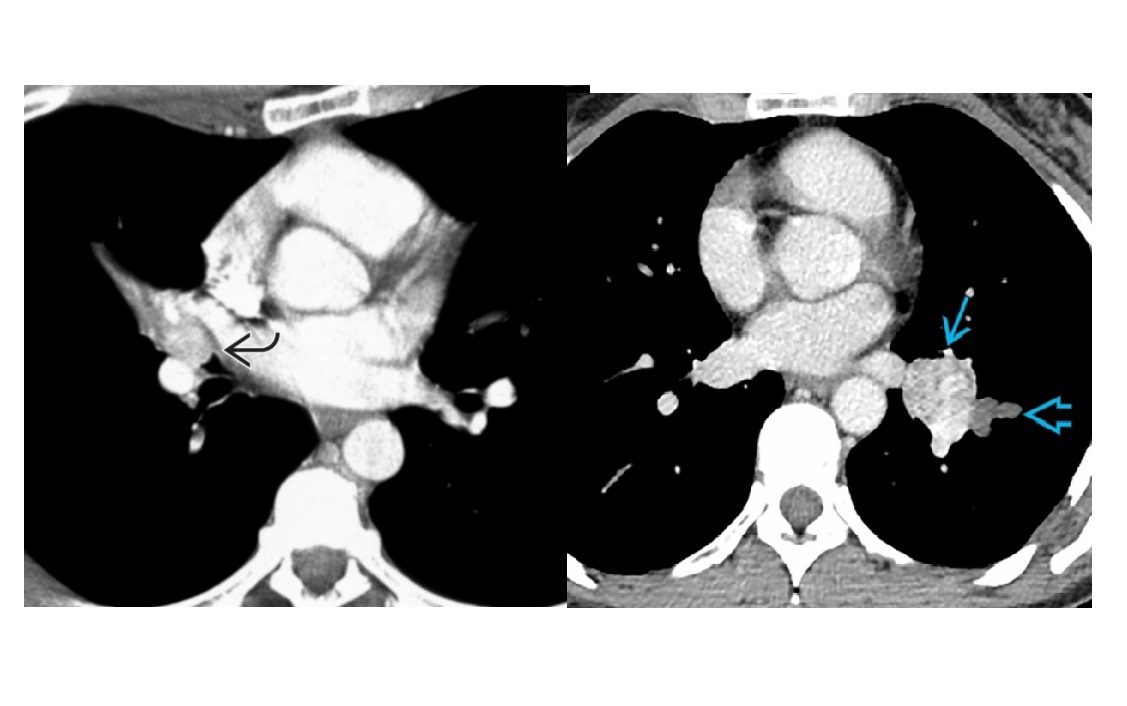

Septic emboli

Peripheral wedges shaped densities +/- cavity

Lower lobe predominant